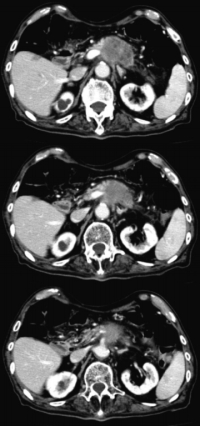

血液所見:赤血球 395 万、Hb 12.9 g/dL、Ht 38 %、白血球 8,100。血液生化学所見:総蛋白 6.7 g/dL、総ビリルビン 0.7 mg/dL、AST 44 U/L、ALT 41 U/L、ALP 522 U/L (基準 115〜359)、γ-GTP 164 U/L (基準 8〜50)、アミラーゼ 51 U/L (基準 37〜160)、尿素窒素 13 mg/dL、クレアチニン 0.8 mg/dL。CEA 758 ng/mL (基準 5以下) 、CA19-9 950 U/mL (基準 37 以下)。腹部造影CTを別に示す。